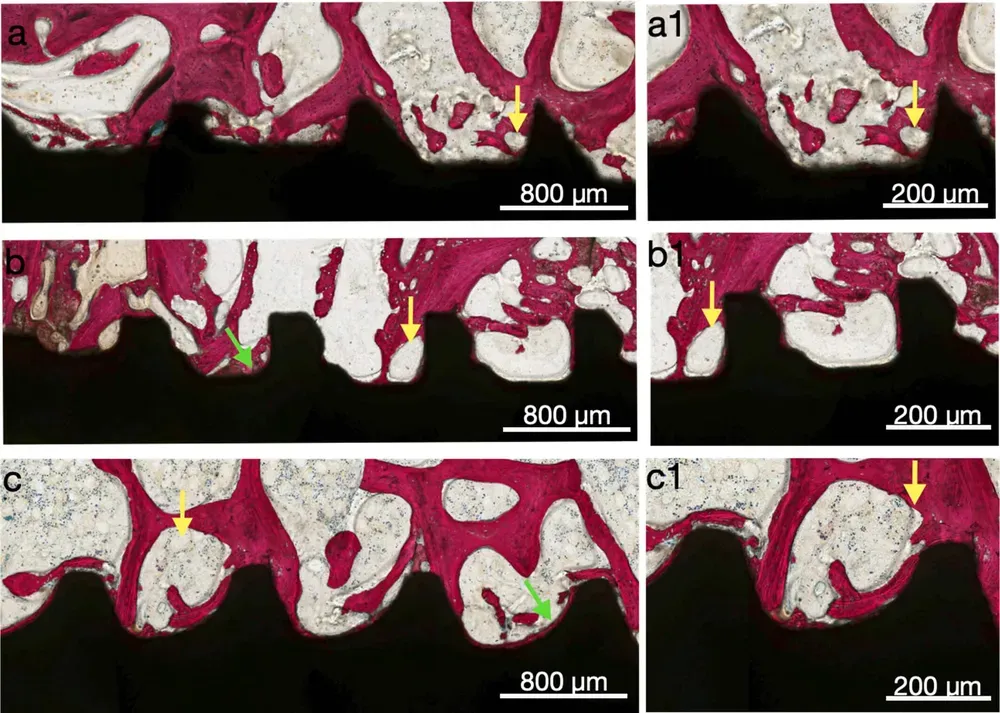

Le immagini sottostanti, tratte dal sopracitato articolo, dimostrano a tre e sei settimane come le camere di guarigione stimolano visibilmente la neoformazione ossea al loro interno (tratto da Benalcázar-Jalkh et al., 2025, licenza CC 4.0)

Gehrke et al. hanno mostrato che gli impianti con healing chambers (le “camere di guarigione” di cui sopra), anche in osso a bassa densità, presentano maggiore quantità di osso sulla superficie dopo il test di pull-out rispetto ai design convenzionali (Gehrke, Scarano et al., 2021). In uno studio su tibia di coniglio, gli stessi autori hanno confermato che le camere di guarigione producono valori di ossificazione superiori rispetto ai filetti convenzionali a “V” e a filetto quadrato (Gehrke et al., 2019).

Benalcázar-Jalkh et al. hanno dimostrato in un modello su pecora che l’effetto sinergico tra macro-geometria con camere di guarigione e vari trattamenti di superficie incrementa significativamente il contatto osso-impianto nelle fasi precoci dell’osteointegrazione (Benalcázar-Jalkh et al., 2025). La superficie giusta, nella forma giusta, fa la differenza.